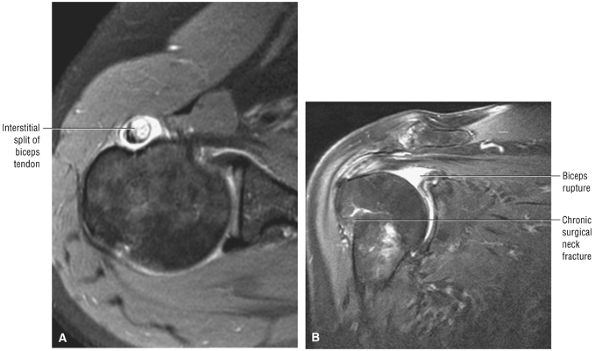

stripped from its lesser tuberosity attachment. However, because of an intact connection with the transverse humeral ligament, which connects the subscapularis tendon to the greater tuberosity, the tendon fibers appear to course in continuity without retraction. Proximal biceps tendon and subscapularis tendon pathology commonly coexist, since the pathogenesis of tendinosis and tears of both tendons are interrelated.